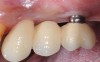

An important aspect of both professionally and patient-administered plaque removal is the cleanliness of the implant-supported restoration. A cohort study on 23 patients demonstrated that 74% of implants had no accessibility to proper oral hygiene and 48% of implants presenting with peri-implantitis were those that were not cleansable.17 The non-fitting or non-cleansable overhanging prostheses, therefore, should be considered iatrogenic factors that contribute to the development of peri-implantitis. Similarly, incorrectly positioned implants or foreign bodies such as impression material or excess luting cement can contribute to increased biofilm accumulation and hence favor the development of peri-implant diseases.10 Correction or elimination of these factors (eg, prosthesis removal and adjustment/replacement, if necessary) should be a principal component of the treatment of peri-implant mucositis (Figure 9 through Figure 11).

Fig 9. Treatment of peri-implant mucositis: plaque accumulation and mucosal inflammation.

Figure 9

Fig 10. Traumatic impingement of the pontic on the peri-implant mucosa.

Figure 10

Fig 11. After thorough mechanical debridement and modification of the prosthesis to allow cleansing.

Figure 11